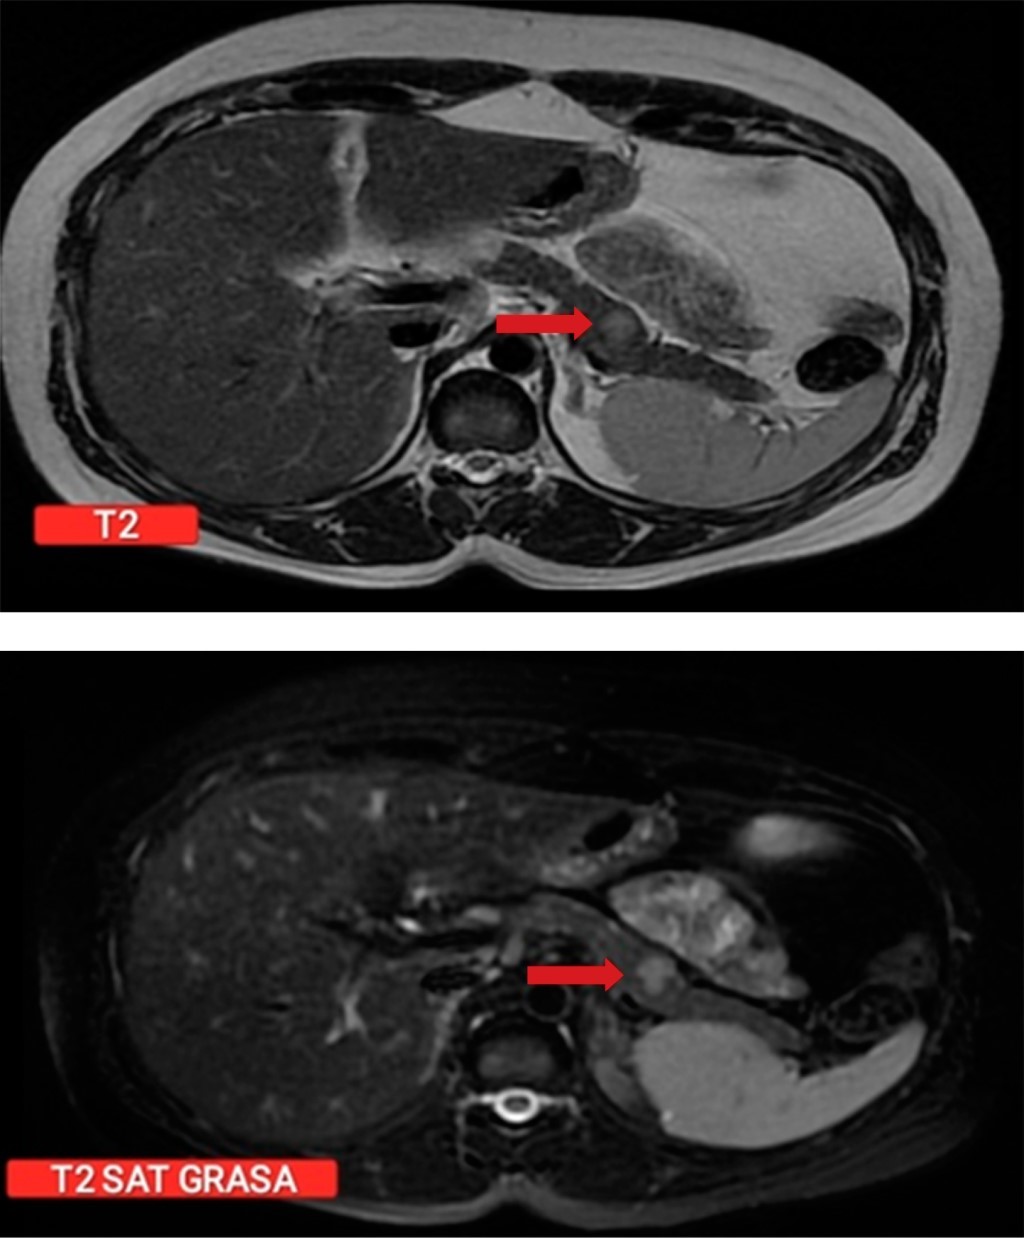

Por cuadro de hipoglucemia severa y recurrente no asociado a la ingesta de antidiabéticos o hipoglucemiantes exógenos se realiza prueba de ayuno de 72 horas con medición de niveles de glucosa e insulina, constatando hipoglucemia con niveles normales de insulina; se realiza tomografía de cráneo y de silla turca sin encontrar lesiones; sin embargo, en la tomografía de abdomen resalta la presencia de un aumento focal en el tamaño de glándula suprarrenal, por lo que se decide caracterizar con resonancia magnética de abdomen en la que se identifica lesión focal única de 13 × 10 mm en la unión del cuerpo y cola pancreático (Figura 1), descrita como hipointensa en secuencias T1 técnicas de saturación grasa (FAT SAT), ligeramente hiperintensa en secuencias T2 con discreto realce periférico tras la administración de contraste y restricción en secuencia Diffusion-weighted Magnetic Resonance Imaging (DWI) y mapa coeficiente de difusión aparente (ADC).

Figura 1